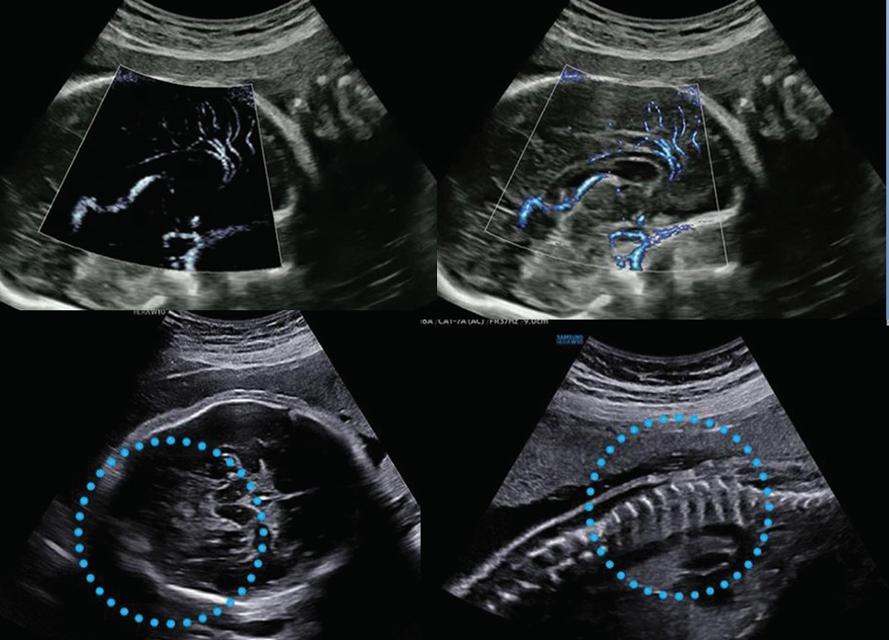

구체적인 기능을 보면 MV-Flow™는 기존 영상에서 검출하지 못했던 저속, 미세 혈류를 시각화하는 기능이다. 고위험 태아의 진단에 도움을 준다.  LumiFlow™는 혈류 (Color, MV-Flow, S-Flow)를 입체적으로 시각화하는 기능이다. 혈류 및 작은 혈관의 구조를 빠르고 직관적으로 이해할 수 있도록 돕는다.

ShadowHDR™은 카메라의 HDR(High Dynamic Range) 기술을 의료용 영상에 접목하고, 초음파의 고주파와 저주파를 선택적으로 적용했다. 태아의 뇌나 척추 등에서 음영이 지는 영역을 확인할 수 있게 했다.

▲(윗줄 왼쪽부터)MV-Flow™, LumiFlow™, (아랫줄 왼쪽부터) ShadowHDR™, HQ-Vision™

HQ-Vision™은 실제보다 약간 흐릿하게 보이는 초음파 영상을 개선해 선명하게 표현되도록 하는 영상 처리 기능이다. 인체의 근육이나 인대, 근섬유처럼 미세 한 구조물의 영상을 획득하도록 도왔다.